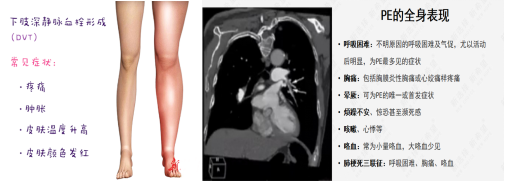

以肺血栓栓塞癥(PTE)為主要臨床類型的肺栓塞(PE)和深靜脈血栓形成(DVT)合稱為靜脈血栓栓塞癥(VTE),是同一疾病在不同階段、不同部位的兩種重要臨床表現(xiàn)形式。臨床上諸多科室的患者均存在VTE風險,其發(fā)病隱匿、臨床癥狀不典型,容易誤診、漏診,一旦發(fā)生,致死和致殘率高; DissolVE-2 研究表明[1],我國的外科住院患者 VTE 中、 高風險比例高達86.1%,內(nèi)科患者 VTE 高風險比例為 36.6%;文獻報道美國每年死于VTE患者25萬至30萬。除了死亡之外,未能及時處理的VTE,多數(shù)不能幸免于深靜脈血栓后遺癥(PTS)的發(fā)生,造成患者長期病痛,影響生活和工作能力,嚴重者可致殘。

下肢深靜脈血栓(DVT)的觀察及護理:

肺栓塞(PE)的觀察及護理:

下肢DVT最嚴重的并發(fā)癥是肺栓塞。肺栓塞急性期病人應絕對臥床休息10~14天,床上活動時避免動作幅度過大,禁止按摩、擠壓或熱敷患肢,保持大便通暢,避免屏氣用力的動作,以防血栓脫落。若病人出現(xiàn)胸痛、呼吸困難、血壓下降等異常情況,提示可能發(fā)生肺栓塞,應立即囑病人平臥,避免做深呼吸、咳嗽、劇烈翻動,同時給予高濃度氧氣吸入,并報告醫(yī)師,配合搶救。